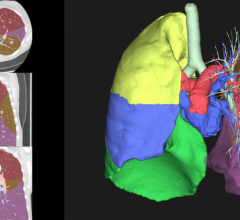

April 27, 2020 — Computed tomography (CT) scans for people at risk for lung cancer lead to earlier diagnoses and improve ...

April 22, 2020 — Siemens Healthineers has received clearance from the Food and Drug Administration (FDA) for its AIDAN ...